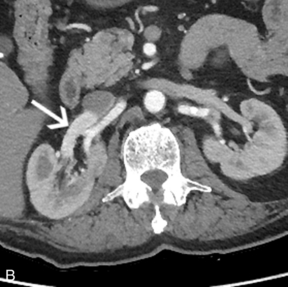

Артериовенозная фистула в нативной почке встречается редко, за исключением случаев предшествующей биопсии почки, и ее нельзя заподозрить при сонографии, если не проводится цветная или энергетическая допплерография. Цветной или энергетический допплер обычно показывает большое извилистое скопление сосудов. Спектральные допплеровские сигналы почечных артерий, питающих фистулу, покажут высокую скорость и низкое сопротивление ( рис. 9-19 ). Основная почечная вена может быть расширена, а в венах вблизи фистулы могут обнаруживаться артериализованные волны ( рис. 9-20 ).

РИСУНОК 9-20. Артериовенозная фистула. (А) Спектральная допплерография демонстрирует артериализованный венозный поток с высокими скоростями и низким сопротивлением. (B) КТ-ангиография показывает раннее усиление правой почечной вены (стрелка) по сравнению с левой почечной веной.